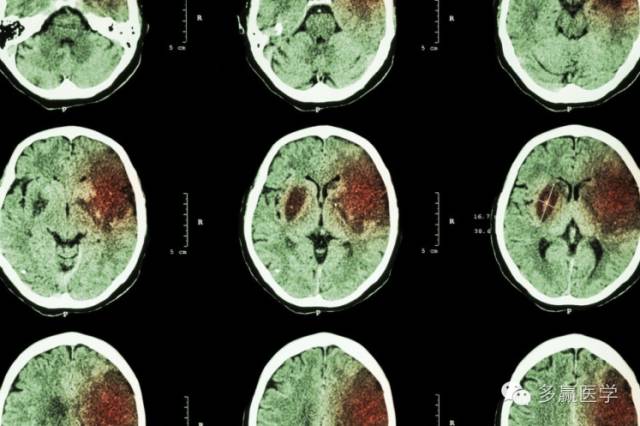

CT扫描一个入组病人的脑部